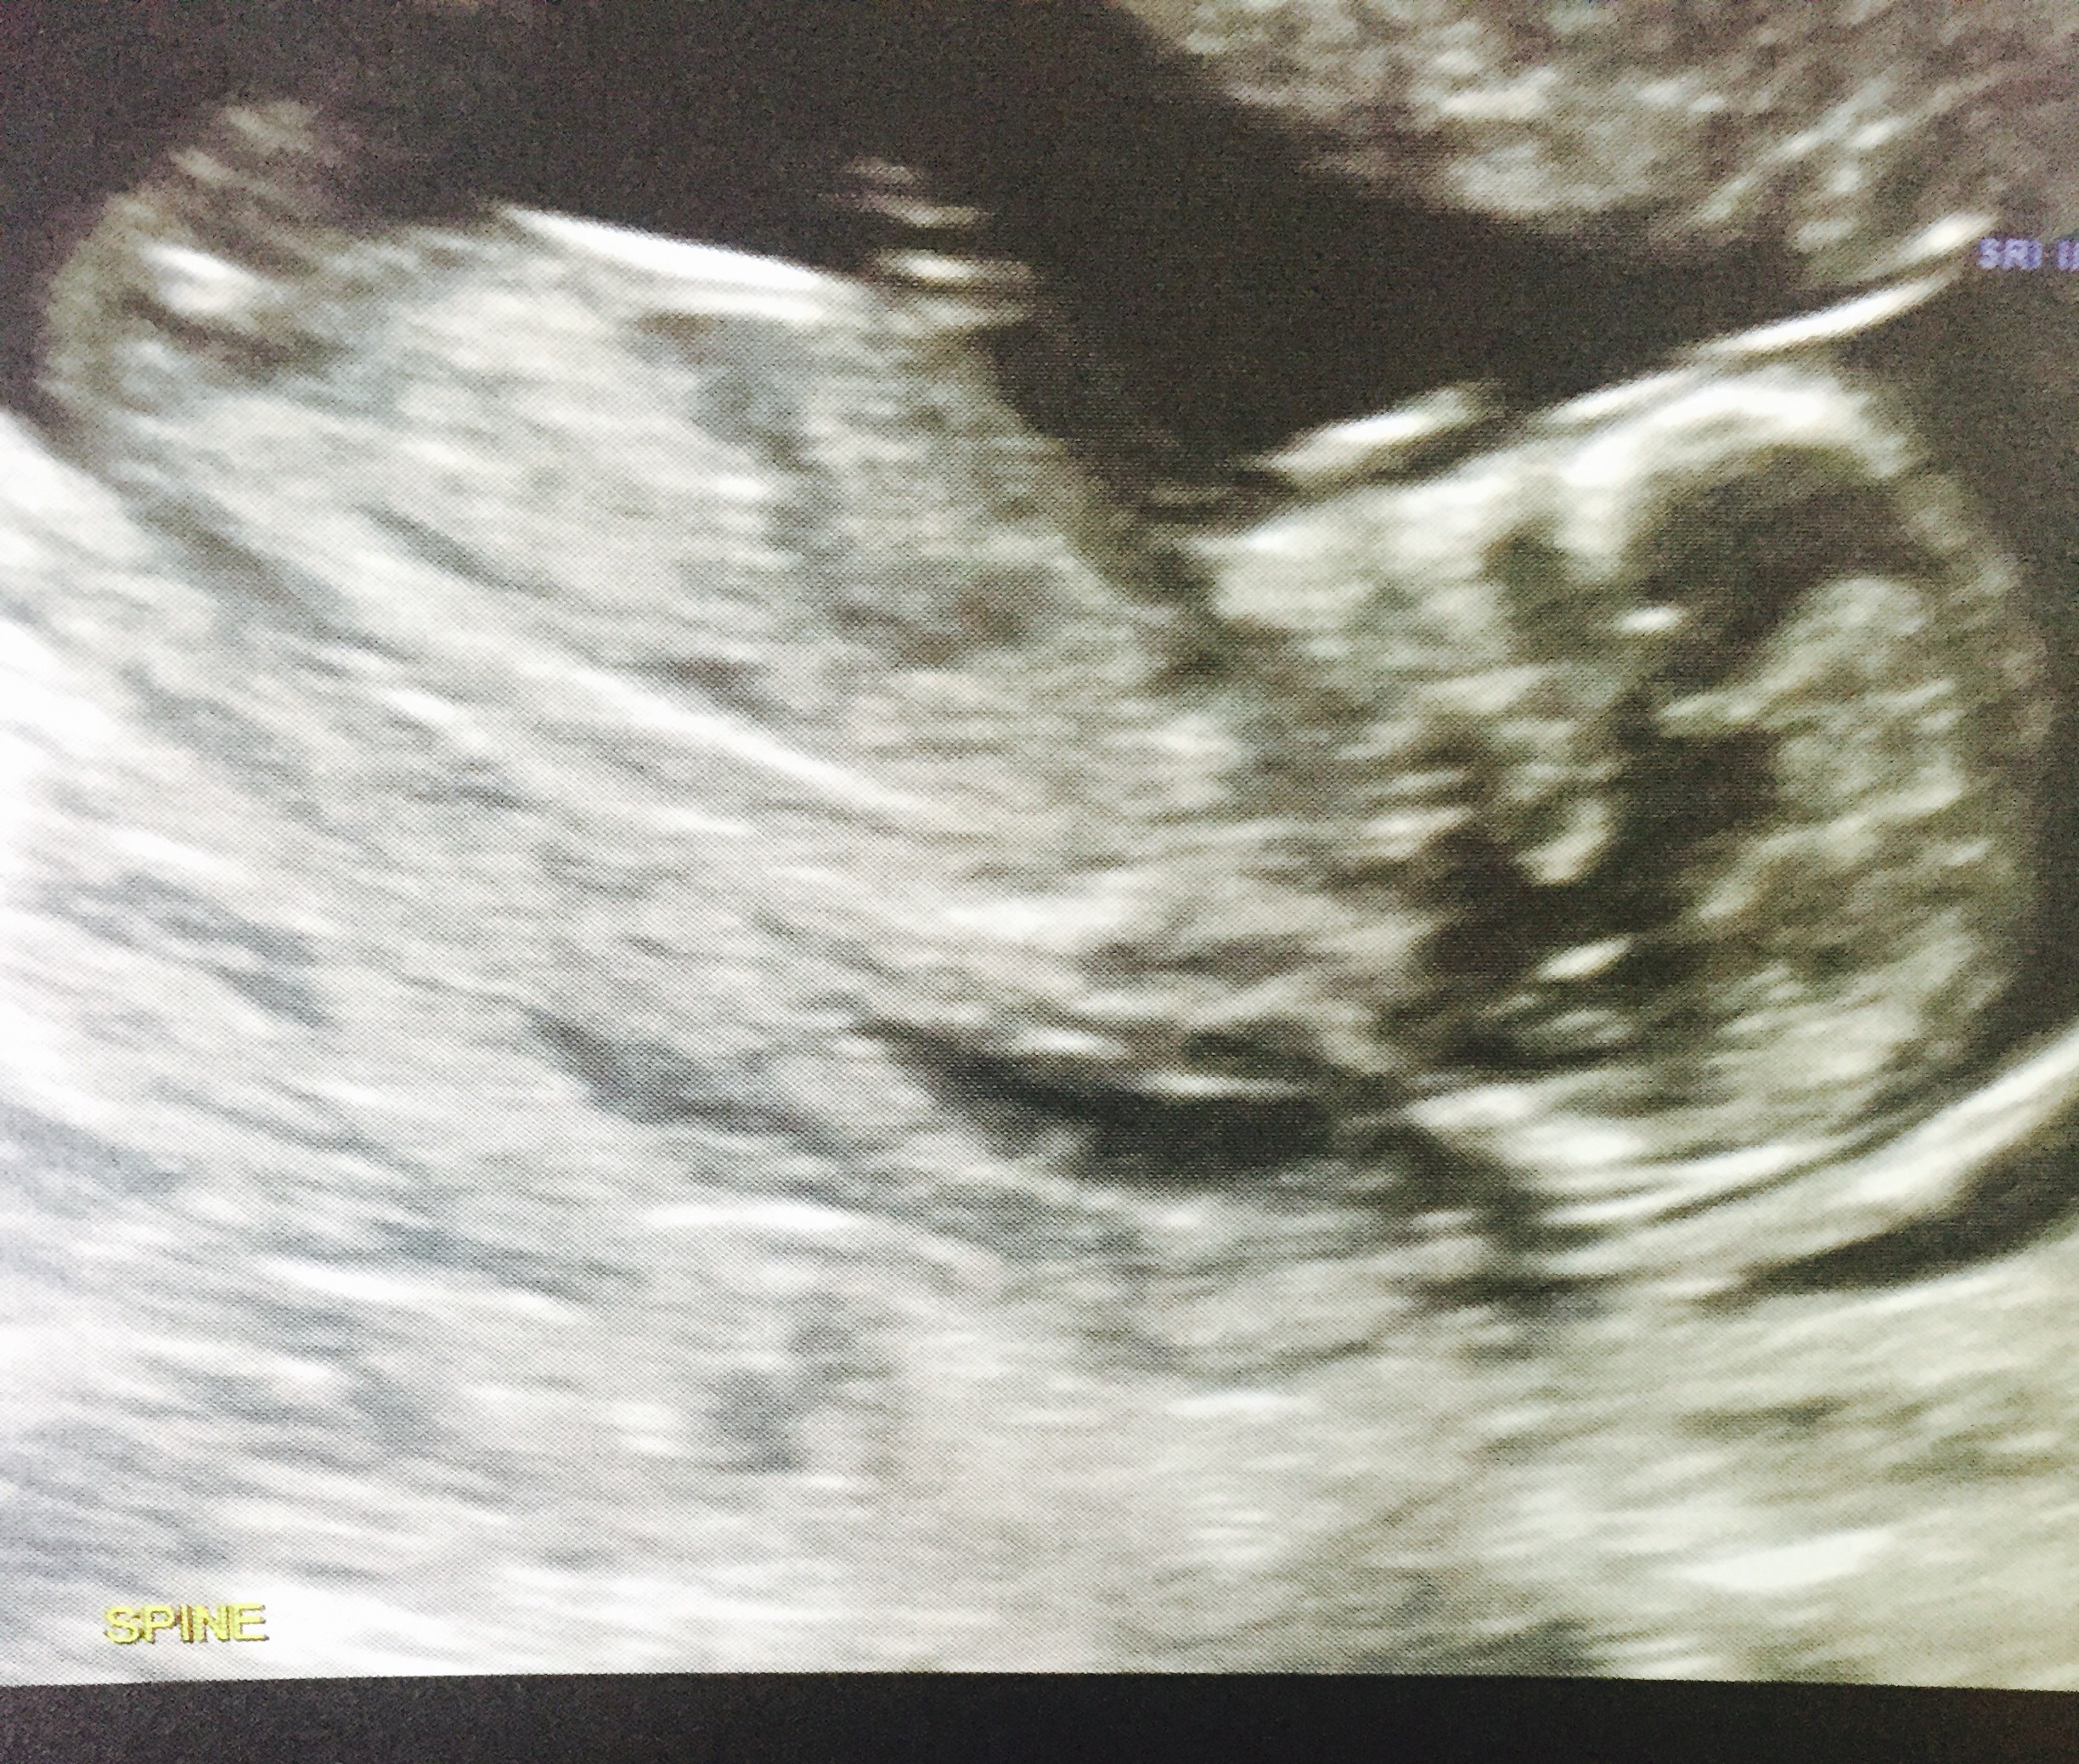

This is from my 13 week scan, I know it looks obvious - but would everyone agree that this is defiantly a boy at this stage??? or do I still have a chance of my little girl?? Opinions welcome x

Very boyish nub

I have this photo as well, which doesn't look anywhere near as 'boyish' as the top one, that's why I'm wondering if it could possibly be the cord or something in the first one? ..... or am I just dreaming? lolAttachment 26406

Leaning girl